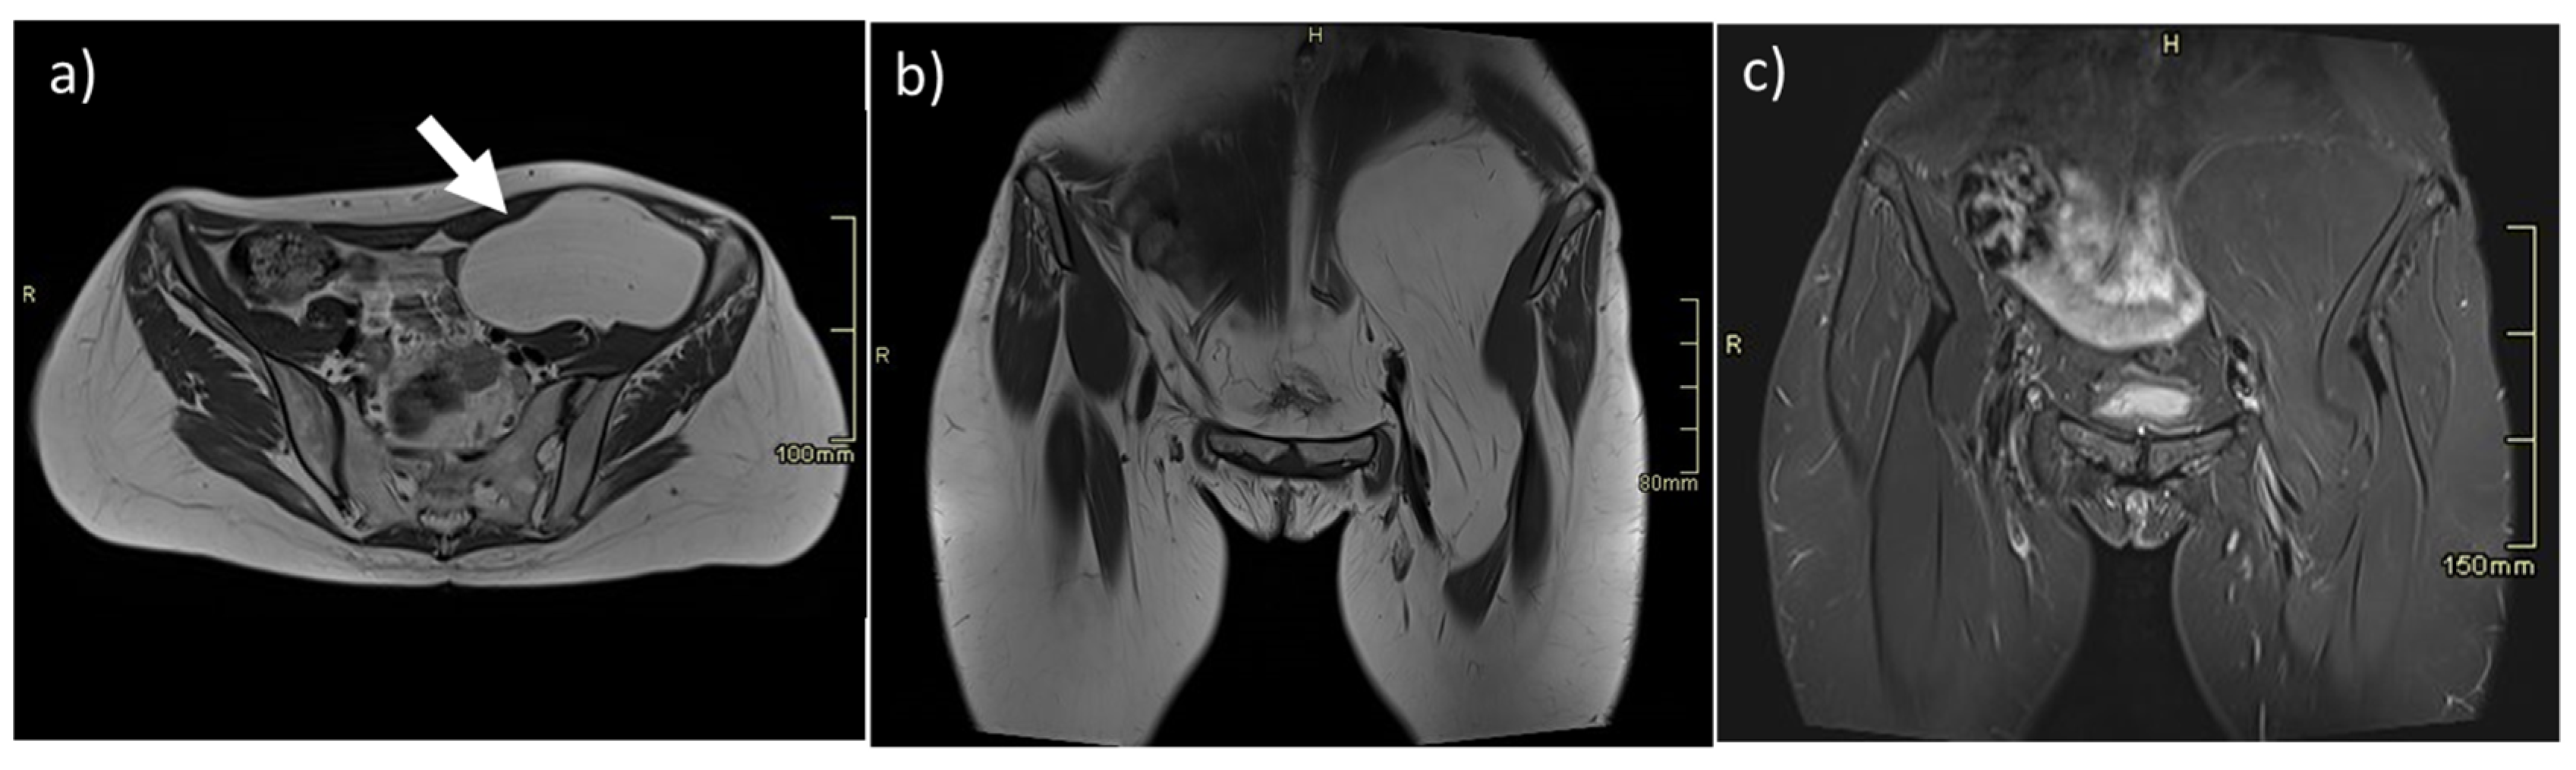

- Leiomyosarcomas: seen on the abdominal wall as either a primary process or as an extension of an intra-abdominal process [23,24]. Leiomyosarcomas demonstrate heterogeneous attenuation and signal intensity, with irregular peripheral enhancement and enhancing solid portions, mixed with hemorrhagic and necrotic areas [24]. Fatty components are absent (Figure 9) [23,24].

- Desmoplastic Small Round Cell Tumor (DSRCT): rare, highly aggressive sarcoma of adolescents, which primarily involves the serosal surfaces of the abdominal cavity infiltrating the abdominal wall [30,31,32]. Classic findings include bulky multiple, hypoattenuating, soft-tissue masses, with omental, serosal, and rectovesical involvement [31,32] and typical punctate or amorphous calcifications [32]. Modest heterogeneous enhancement is seen on arterial phase, without prolonged enhancement or portal washout [31,32] (Figure 10). On MR, DSRCTs are heterogeneously iso- to-hypointense on T1-w images, with hyperintense foci due to intratumoral hemorrhage [32].